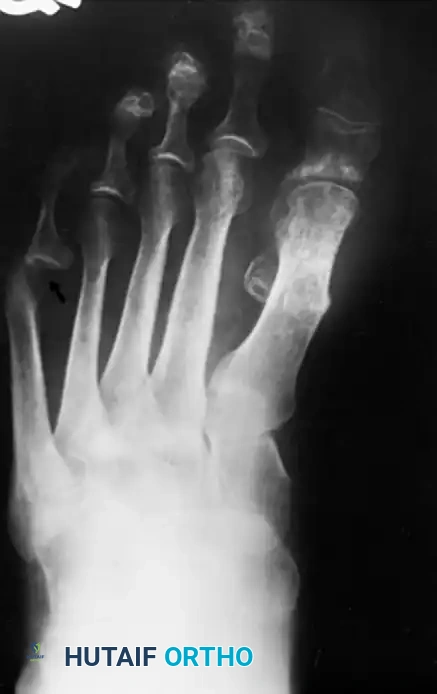

In contemporary orthopedic practice, a bunionette is frequently observed as part of a broader forefoot pathology, most notably the splay foot deformity combined with hallux valgus. The etiology is multifactorial. The head of the fifth metatarsal may be congenitally or traumatically enlarged (Type I deformity). Alternatively, the diaphysis may be angulated laterally (Type II deformity), or there may be a widened fourth-fifth intermetatarsal angle (Type III deformity), making the fifth metatarsal head excessively prominent.

Fig. 80-30 A and B, Bunionette with metatarsus quintus valgus and fifth toe varus.

Fig. 80-31 Bunionette–hallux valgus–splay foot complex. Note lateral angulation of shaft of fifth metatarsal at distal third (arrows).